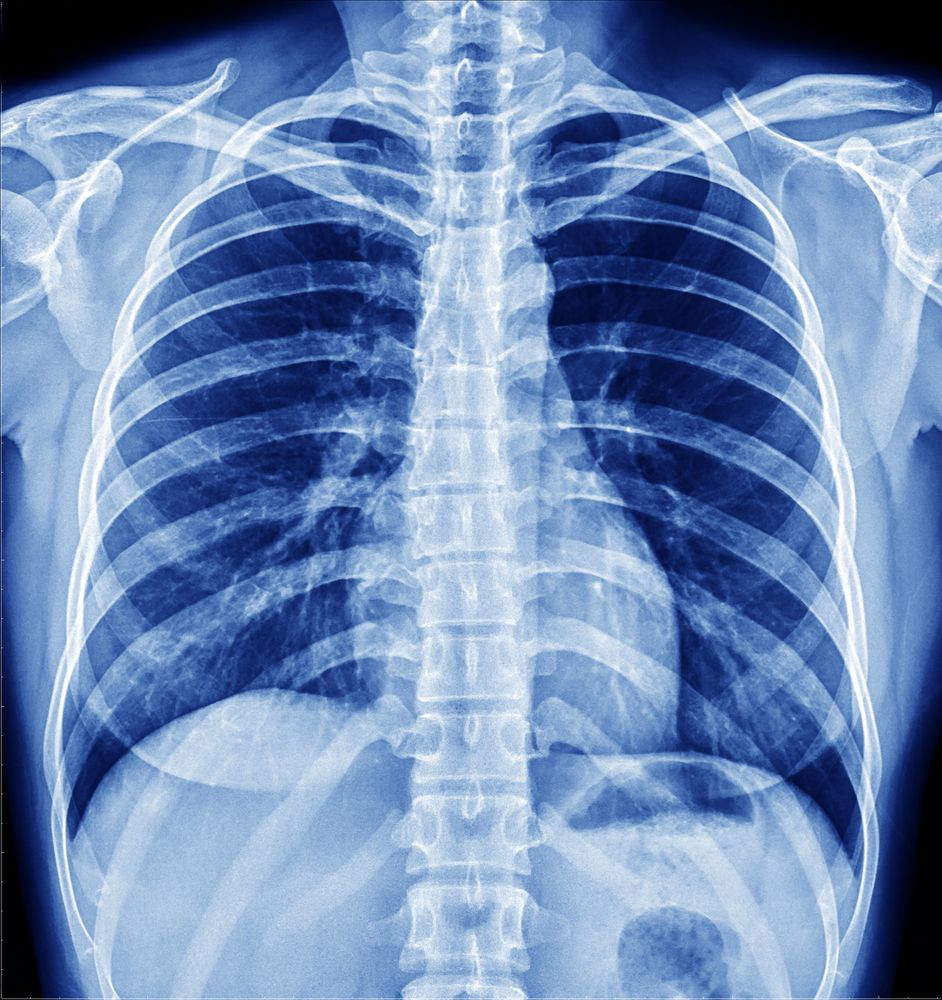

Nhờ các thực nghiệm, ông biết rằng tia X xuyên qua da thịt người nhưng không để xuyên qua những chất có mật độ cao như xương hoặc chì, và chúng có thể được chụp ảnh lại.

Phát hiện của Rontgen được xem là một phép màu y học thời đó, và tia X sớm trở thành một công cụ chẩn đoán quan trọng trong y học, cho phép các bác sĩ nhìn thấy bên trong cơ thể người mà không cần phẫu thuật.